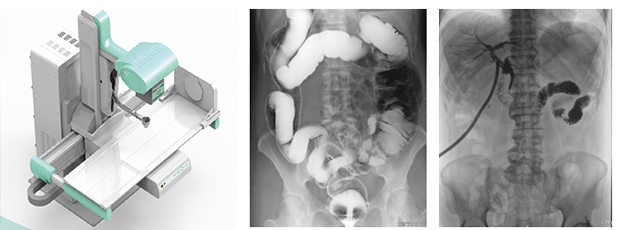

多功能dr集合拍片、造影、胃腸、透視等多種功能??梢岳斫鉃橐环N不同角度觀察器官運(yùn)動的X光視頻,可以從不同的角度、時間來觀察器官的運(yùn)動,診斷準(zhǔn)確率會大大提升。面對常規(guī)dr誤診漏診頻繁出現(xiàn)的情況,多功能dr是如何用其產(chǎn)品優(yōu)勢彌補(bǔ)缺陷的?接下來小編帶大家先來看一組動態(tài)臨床案例。

由此可見,多功能dr所采用的數(shù)字探測器,全幀技術(shù)可以得到盡量大的光電二極管,能夠輸出更穩(wěn)定清晰的影像質(zhì)量。數(shù)字高壓技術(shù)具有高壓快門,能夠在毫秒級時間內(nèi),實現(xiàn)高壓的切換。超級圖像處理技術(shù)采用雙通道算法以及并行圖像處理技術(shù)。多功能dr的探測器為17×17 ,完全可以在同一個屏幕中獲取整個檢查部位的視野,便于觀察。

其次采用多功能dr視頻采集技術(shù),經(jīng)過一次順利的檢查后保存視頻,可以實時回顧分析采集圖像,也有利于疾病的隨訪、對比及會診。此外,在骨科診斷過程中,由于隱匿性骨折范圍小、程度輕,即使使用CT檢查敏感性也不高,MRI檢查費(fèi)用過于昂貴,而用多功能dr透視下的多軸位點片,可以明確隱匿性骨折的診斷,是避免誤診隱匿性骨折的有效辦法之一。